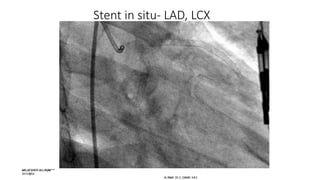

Stent in situ- LAD, LCX

LAD stent in situ- Osteoprox-Distal part